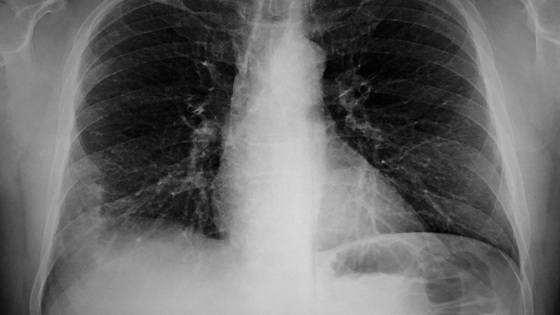

Врач рассказала, как распознать микоплазменную пневмонию

По словам врача Татьяны Ким, возбудителем пневмонии в 20% случаев может быть микоплазменная болезнь. Врач рассказала, какие симптомы характерны для болезни.